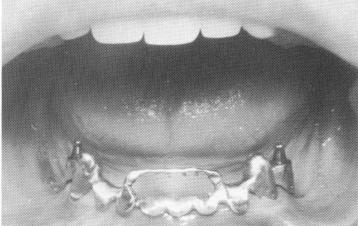

Fig. 13-39. Anteriorly are endodontic stabilizers. Posteriorly are bilaterally placed subperiosteal implants that were used for the endentulous areas because there was not enough alveolar bone for endosseous screws or blades.

1 Endodontic stabilizers in the anterior part of mandible

2 Bilaterally placed subperiosteal implants in posterior mandible